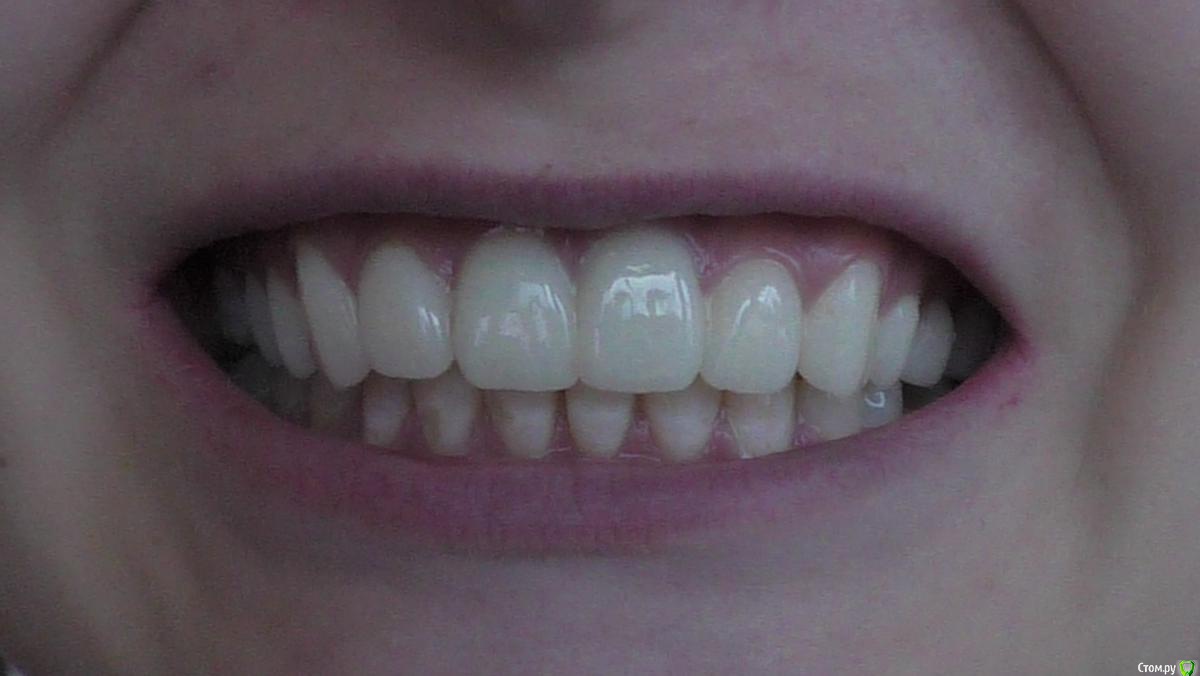

alix Опубликовано 3 ноября, 2017 Автор Поделиться Опубликовано 3 ноября, 2017 Поставили наконец-то керамические коронки (emax). Пока сохраняется чувствительность на накусывание на правой двойке и зубы в целом немного реагируют на горячее\холодное. Что-то более твердое, чем кусок курицы и бутер с сыром есть еще не пробовала. Надо затестить какую-нибудь морковку, но пока страшновато.Смыкание кажется все равно непривычным, но в этот раз техник гораздо лучше подогнал по прикусу, не было явного завышения и мешающих бугров. Возможно, нужно еще немного пришлифовать для полного комфорта.Слегка не угадала с цветом, в кабинете цвет казался нормальным, а дома осознала, что временные были более светлые. Впрочем, сейчас коронки лучше сочетаются с цветом родных зубов и выглядят натуральнее. Так что, может, и к лучшему.В общем, пока все не плохо, беспокоит только хруст в суставах челюсти. Уж не знаю, связано это с новыми коронками или нет. Ссылка на комментарий